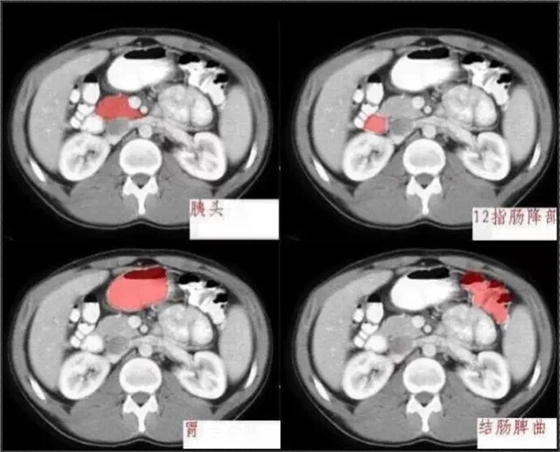

首頁(yè)口腔影像 秒懂:腹部 CT 看這篇就夠

秒懂:腹部 CT 看這篇就夠